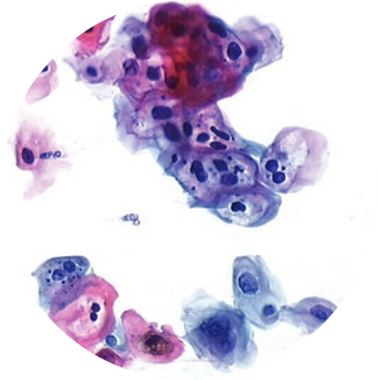

Exame Colpocitológico

A colpocitologia oncótica, também conhecida como exame preventivo ou Papanicolau, é o exame mais utilizado para prevenção do câncer do colo do útero.

Considerando o caráter preventivo do exame colpocitológico, o Lapac esta apto a auxiliar os médicos ginecologistas a fazerem o acompanhamento periódico das suas pacientes através de laudos claros e com rápido tempo de resposta.

Citologia Oncótica Líquidos Cavitários, Secreções e Raspados

Raspados, “imprints”, secreções, líquidos cavitários, escovados, descarga papilar e punções aspirativas por agulha fina.

Em casos de líquidos cavitários as amostras devem ser imediatamente refrigeradas a uma temperatura de 2 a 8º até 24h ou colocadas em recipiente com álcool a 50% em proporção igual ao volume da amostra por ate 7 dias em temperatura ambiente. Em casos de amostras dispostas em esfregaços deve-se fixar em álcool a 95%.